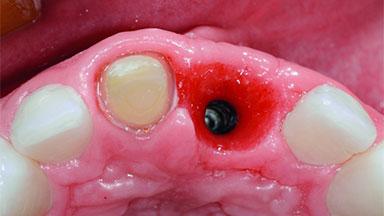

Replacement of an Ankylosed Upper Left Central Incisor: Bone Augmentation and Socket Grafting, Late Placement of an RC Bone Level Implant

| Bone Augmentation | Horizontal|Simultaneous|Staged |

| Augmentation Materials | Autogenous chips|Xenogenous |

| Bone Volume | Deficient horizontally, requiring prior grafting |